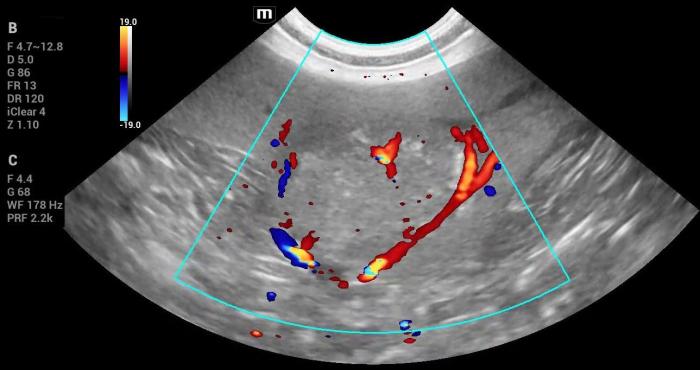

La masa deformaba la arquitectura de la cola esplénica y mostraba vascularización Doppler color positiva, observándose un vaso de gran calibre atravesando toda la masa, sin alteraciones evidenciables (Figura14). No se identificaron otras lesiones esplénicas focales ni alteraciones compatibles con metástasis.

- Vascularización Doppler color positiva (Figura 18-19).

- Doppler positivo.